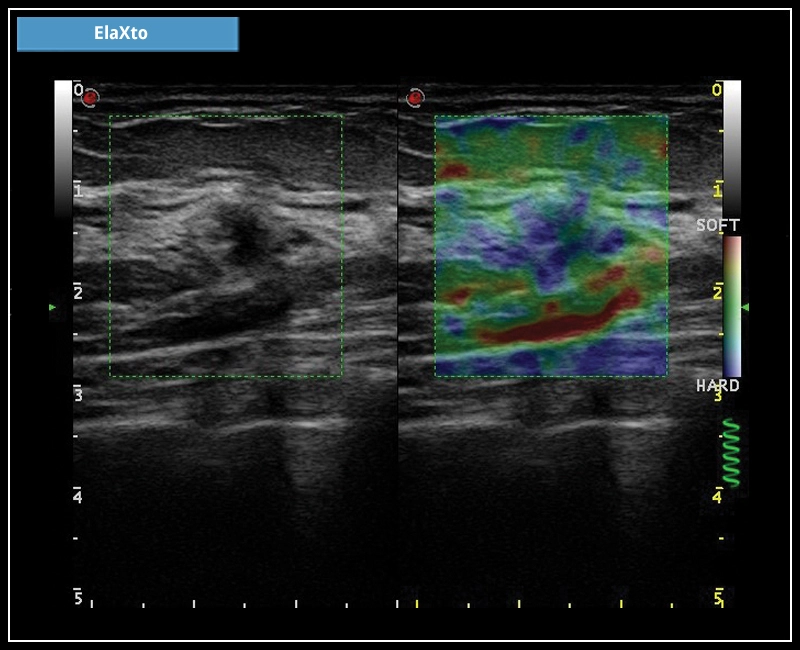

MyLab™X7 - ElaXto

MyLab™X7 - ElaXto